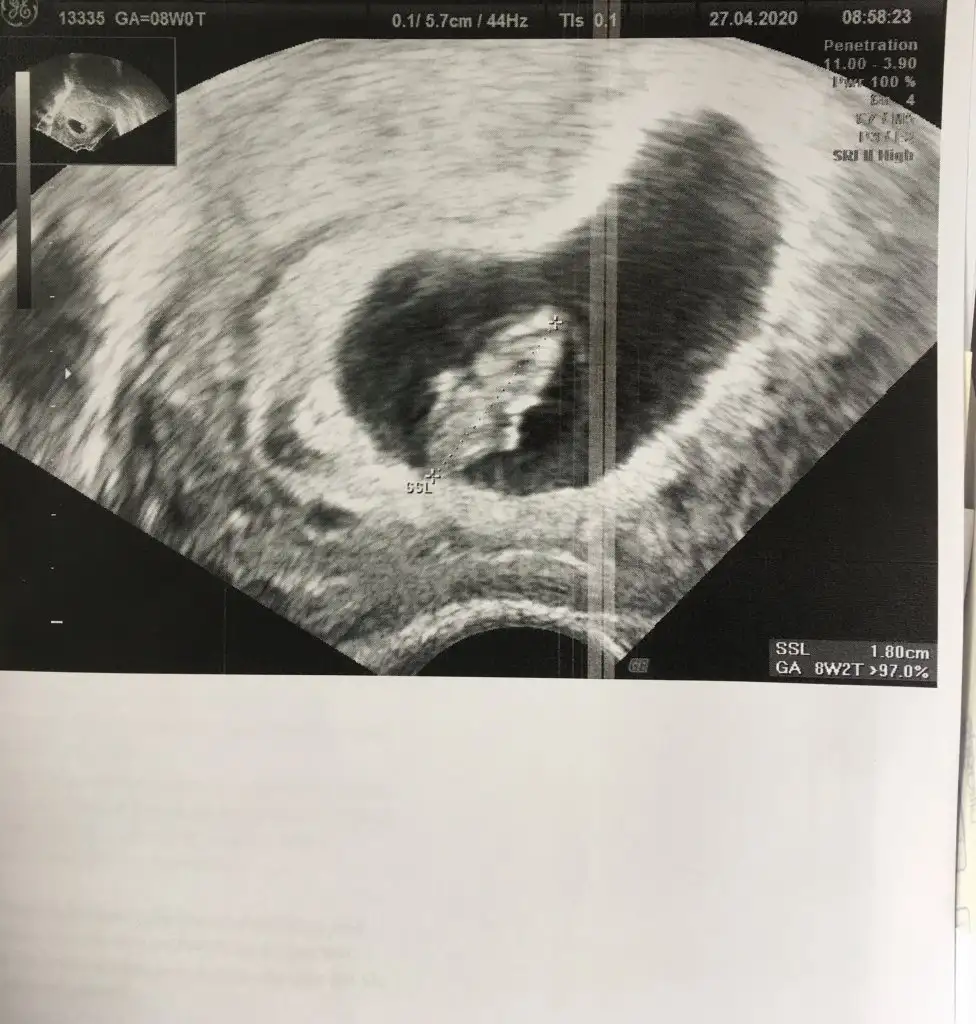

Valla bende 8+0 ultrason görüntüsü var yani ilk ultrason görüntümüz. Az önce baktım öyle kolu bacağı çok net değil şimdiki gibi çok insan görüntüsü yok. Küçük küçük çıkıntılar var sadece ama ileri haftalarda çok daha netleşiyor tabiki. Bak hattaburaya ekliyorum benimkiniAnladımmm bilgiler için teşekkür ederiminsan sabırsız oluyor gerçekten heyecandan galiba..

Oyy yine de baya gelişmiş benim ilk ultrason 6+5 te verildi ve bildiğiniz bir tektaş yüzüğe benziyorduValla bende 8+0 ultrason görüntüsü var yani ilk ultrason görüntümüz. Az önce baktım öyle kolu bacağı çok net değil şimdiki gibi çok insan görüntüsü yok. Küçük küçük çıkıntılar var sadece ama ileri haftalarda çok daha netleşiyor tabiki. Bak hattaburaya ekliyorum benimkiniEki Görüntüle 2664103 Eki Görüntüle 2664103